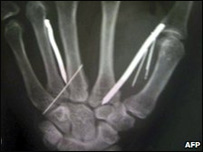

Ariyawathie after surgery

13 nails and five needles removed from her body

Doctors removed 13 nails and five needles from her body.